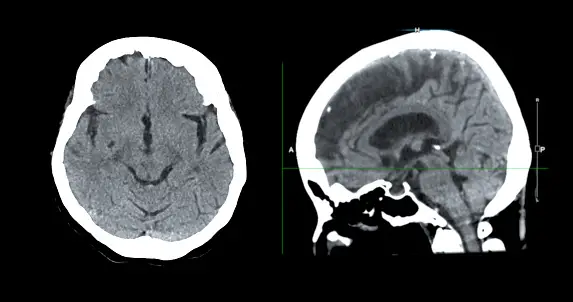

최근 뇌종양 진단 분야에서는 혁신적인 기술이 많이 개발되고 있습니다. 이러한 기술은 기존의 진단 방법에 비해 더 정확하고, 비침습적이며, 빠르게 결과를 얻을 수 있습니다. 예를 들어, 자기공명영상(MRI) 검사는 뇌 구조의 상세한 영상을 제공하여 종양의 위치와 크기를 파악하는 데 사용됩니다. 또한, 양전자방출 단층촬영(PET) 검사는 뇌 활동을 영상화하여 종양의 대사적 특성을 평가하는 데 사용됩니다.

- 자기공명영상(MRI): MRI는 뇌의 상세한 영상을 생성하여 종양의 크기, 위치 및 특성을 평가하는 데 사용됩니다. 종양을 감지하는 대비제를 사용할 수도 있습니다.

- 컴퓨터 단층촬영(CT): CT는 뇌의 단면 영상을 생성하여 뼈와 같은 뇌 구조의 이상을 확인하는 데 사용됩니다. 종양을 강조하기 위해 대비제를 사용할 수도 있습니다.